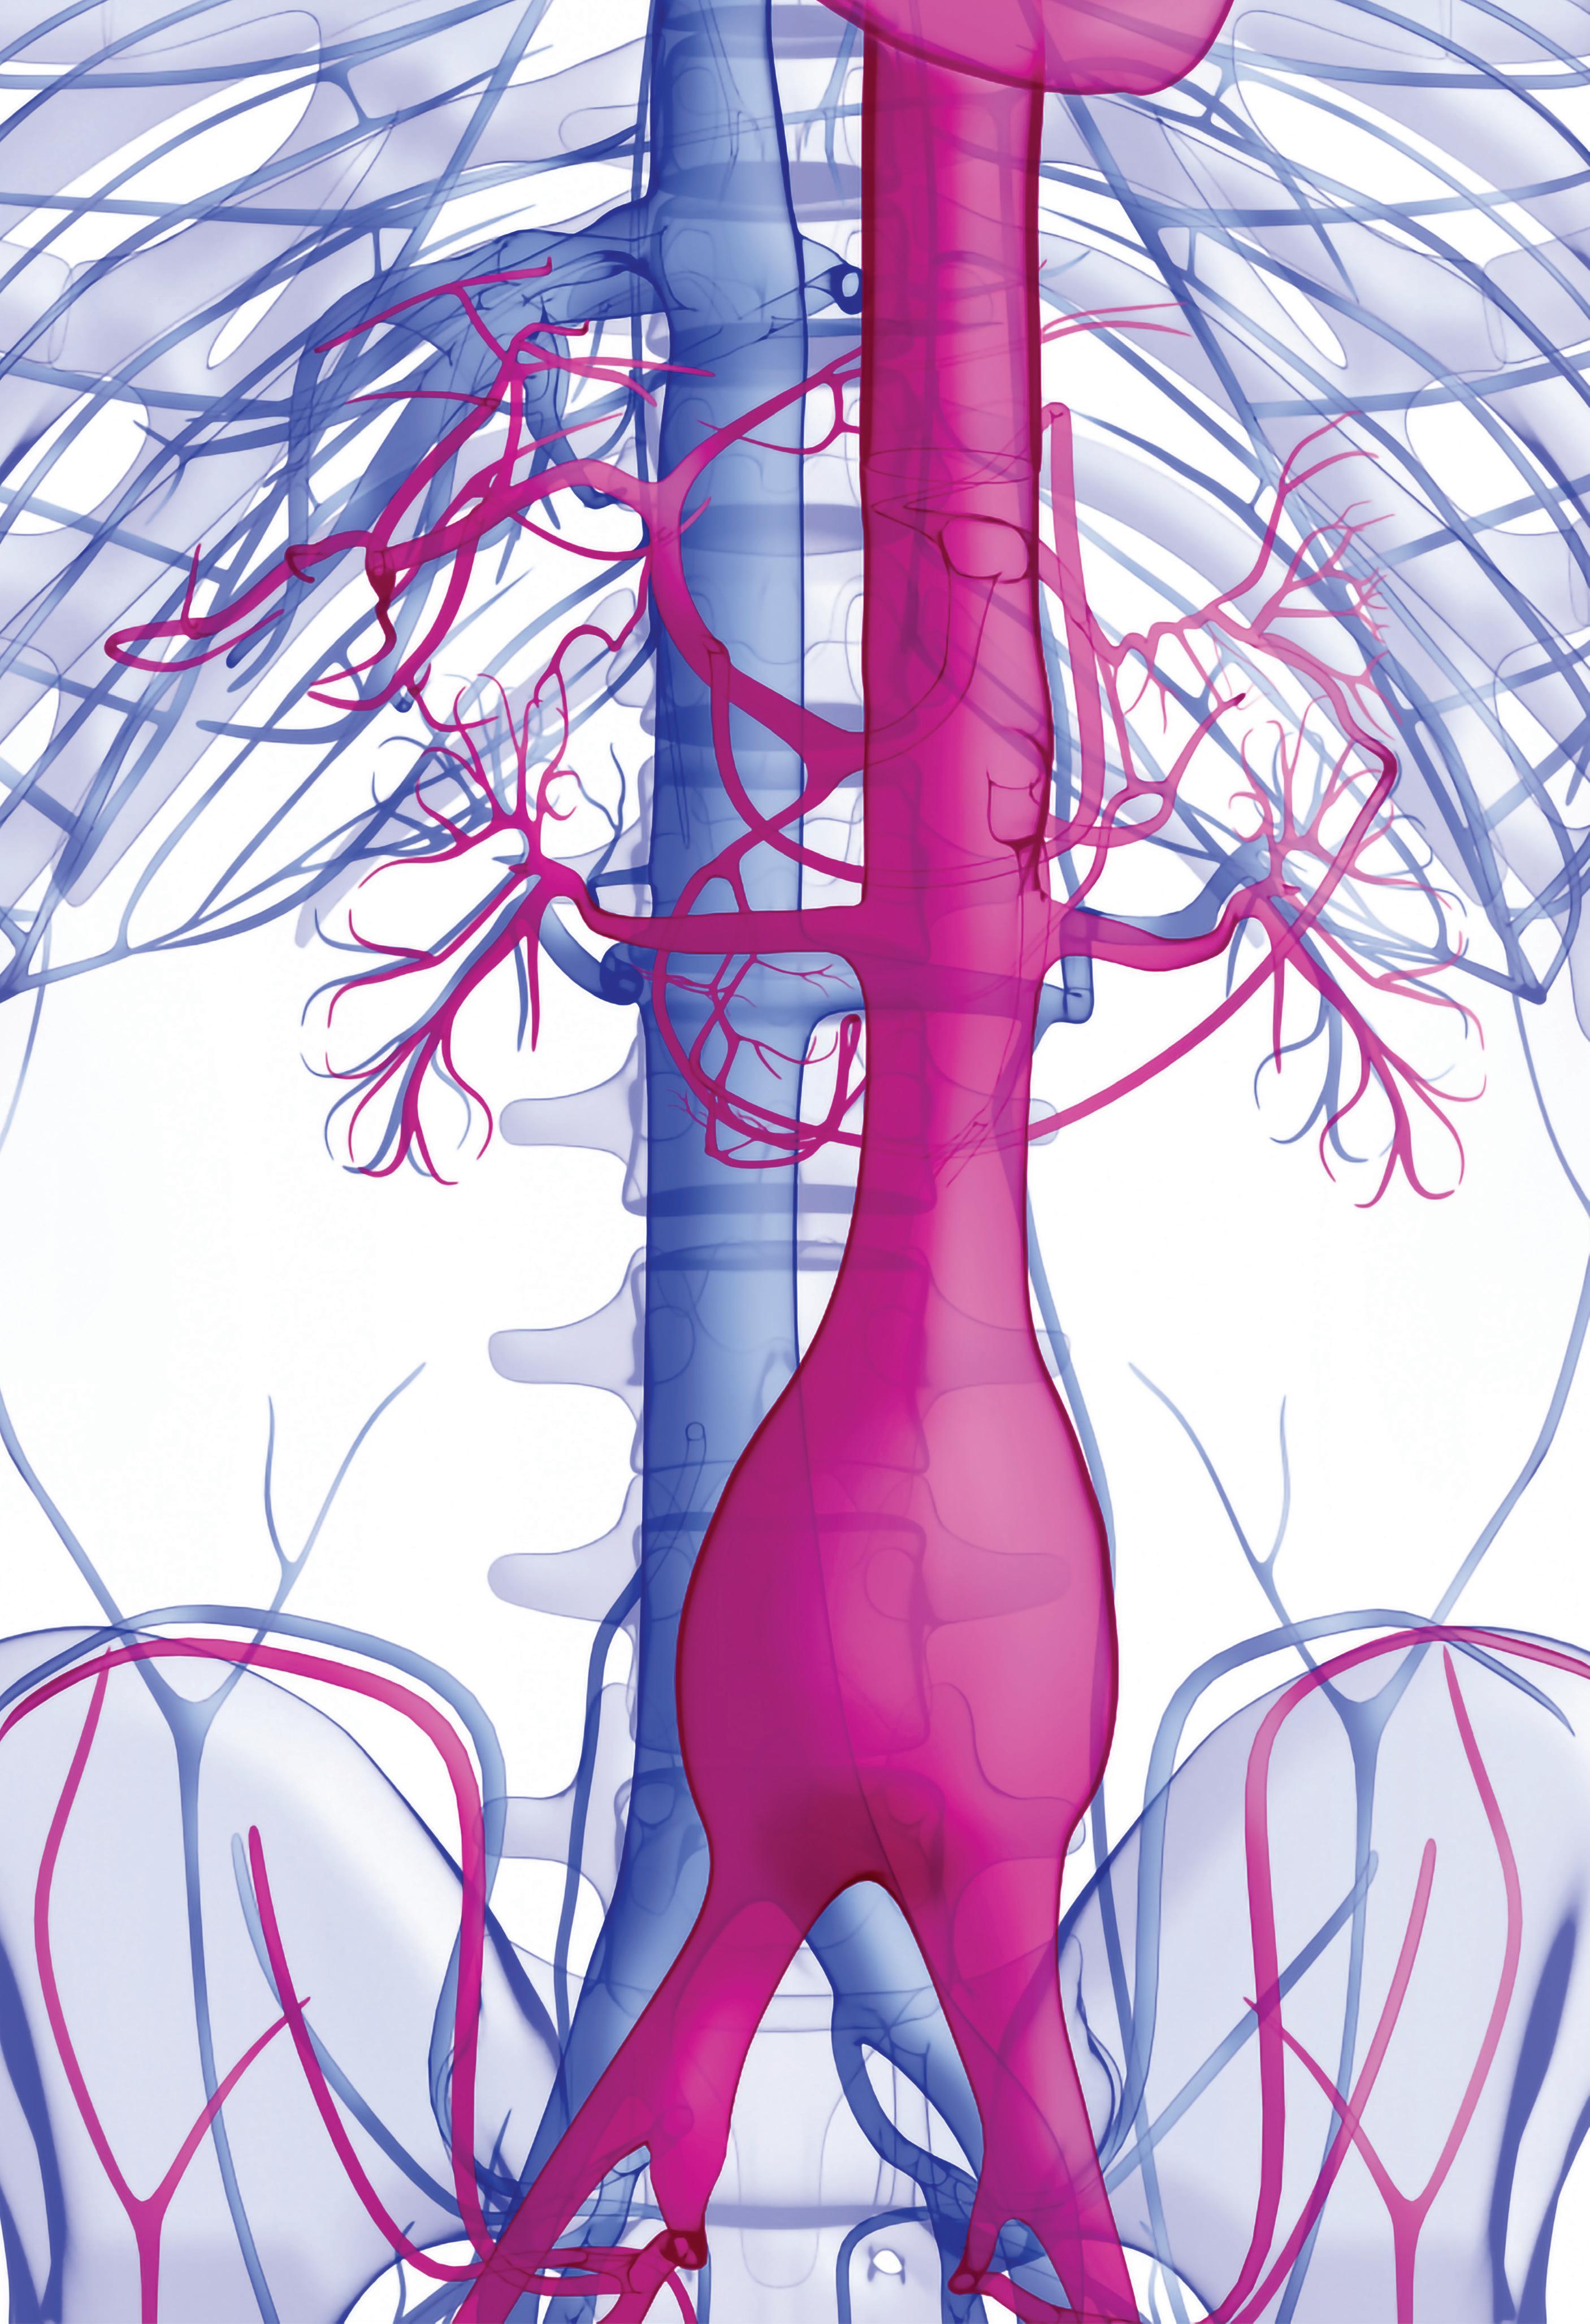

International collaboration key to proliferation of endovascular thoracoabdominal repair

“We have to work together to pool data that demonstrate equivalence or superiority to open surgical repair,” Gustavo Oderich (University of Texas Health Science Center at Houston, Houston, USA) said of endovascular thoracoabdominal aortic aneurysm (TAAA) repair at this year’s European Society for Vascular Surgery (ESVS) annual meeting (20–23 September, Rome, Italy). He stressed that while the technique is “here to stay,” it is one that will require international, multicentre collaboration in order to be seen as on a par with, or even superior to, the current “gold standard” of open repair.

Now, three decades later, Oderich remarked that the vascular community has “embraced” endovascular therapy in many areas of the aorta and for a variety of pathologies, ranging from aneurysms to dissections. “However,” he noted, “there are areas of the world where endovascular repair of TAAAs is still not considered the first line of treatment”.

What do the data say?

Society clinical practice guidelines on aortic disease, which Oderich noted are being updated and will be published later this year, state that open thoracoabdominal aortic repair “remains the gold standard” for low- and intermediate-risk patients, at least in the USA. The reason for this, the presenter believes, comes down to the data that are currently available. The data on endovascular repair mostly come from single centres, or series with relatively short follow-up that are “often plagued with high reintervention rates,” he said.

With this in mind, Oderich put forward the key question: “What is the benchmark that we have to compare to, to be able to say—at some point—that endovascular is truly the first line of therapy?”

The speaker first considered the question of mortality. He noted that, despite many advances in critical care and surgical techniques, the mortality rate “in the best hands” for open surgical thoracoabdominal repair averages about 10% for an extent II thoracoabdominal aneurysm. However, the speaker highlighted that only one third of these patients are actually treated in high-volume centres. The majority are treated in mid- or low-volume centres where the mortality is “substantially higher” than it is in high-volume centres, averaging 20%.